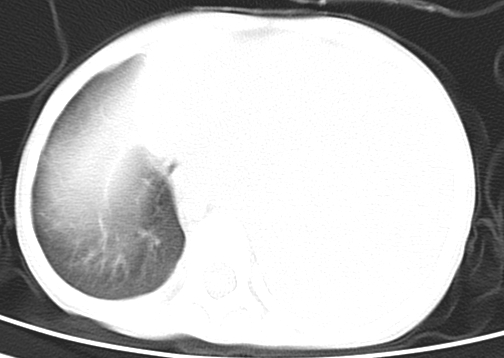

患儿 女 4岁,发热 咳嗽 胸透 考虑:左侧脓胸

左侧胸廓内见大量密实阴影,肺尖部尚有少量肺组织影,纵膈明显受压移位,肋骨未见明显受侵征象,虽然病人年龄较小,但如此大量的“积液”,还是要警惕,不同意一般感染,可结合穿刺脱落细胞学检查。

1)考虑左肺炎症感染。2)左侧大量胸腔积液。

1)考虑左肺炎症感染。2)未经穿刺只能定左侧大量胸腔积液。

左侧张力性大量胸腔积液压迫性肺不张、感染;建议治疗后复查。